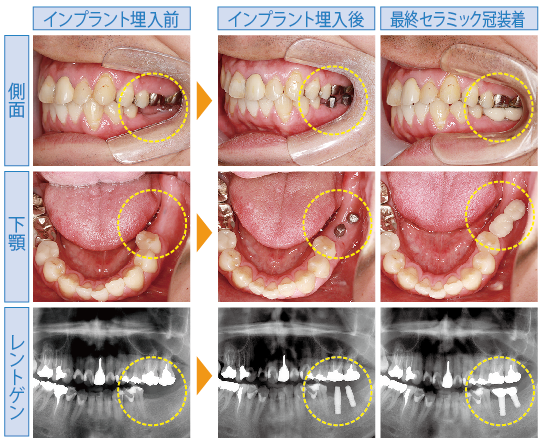

- 左下2本のインプラント治療

- 全顎矯正治療

- 埋入後の疼痛、腫脹。インプラント周囲炎など。